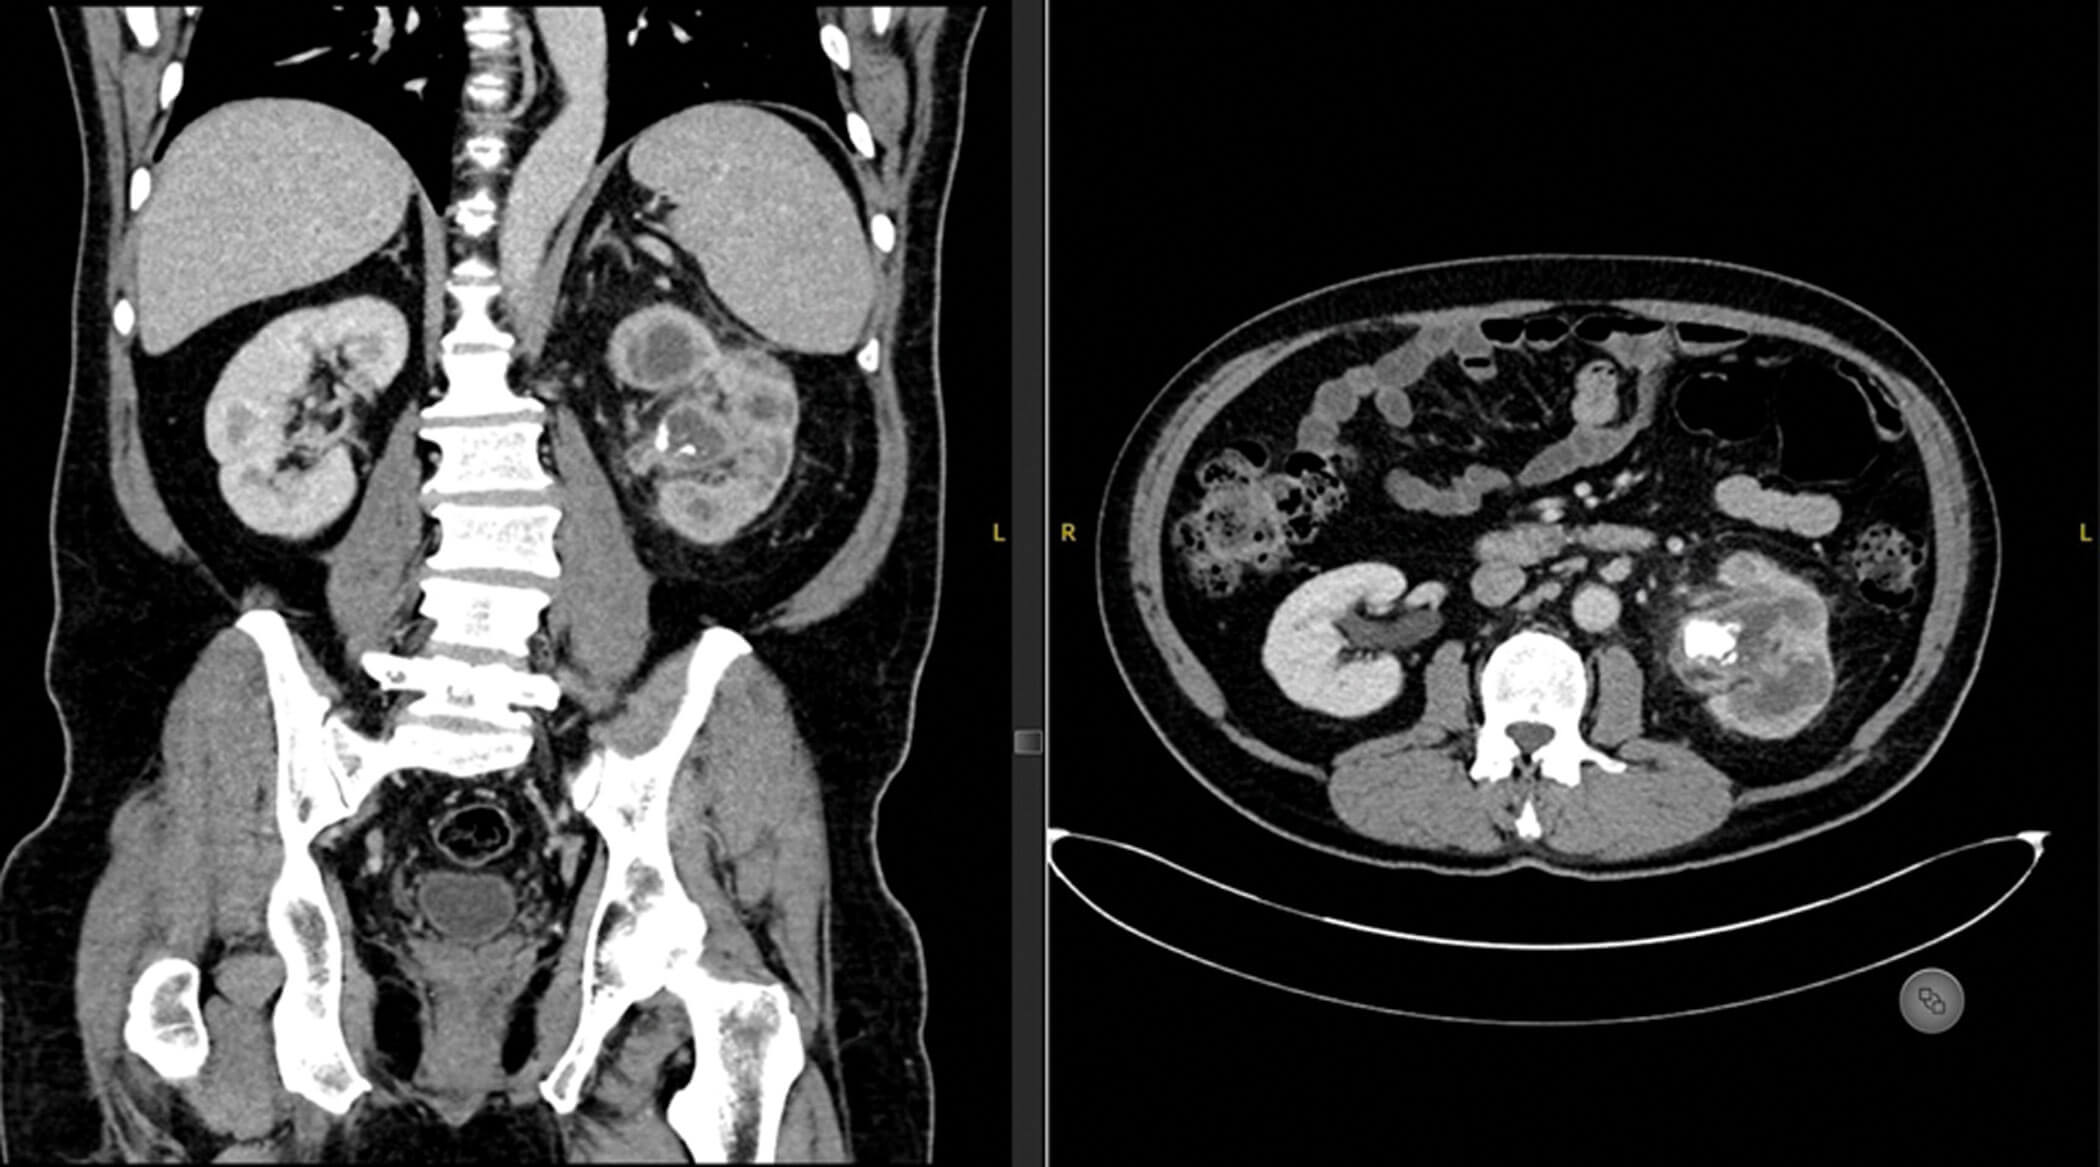

Figure 2.

- This is a coronal and axial contrast enhanced CT scan of an abdomen and pelvis. The most striking abnormality is the left 2.5cm PUJ calculus with calyceal dilatation, loss of renal cortex and perinephric inflammation. Additionally, the appearance is consistent with bear’s paw sign. This is xanthogranulomatous pyelonephritis (XGP).